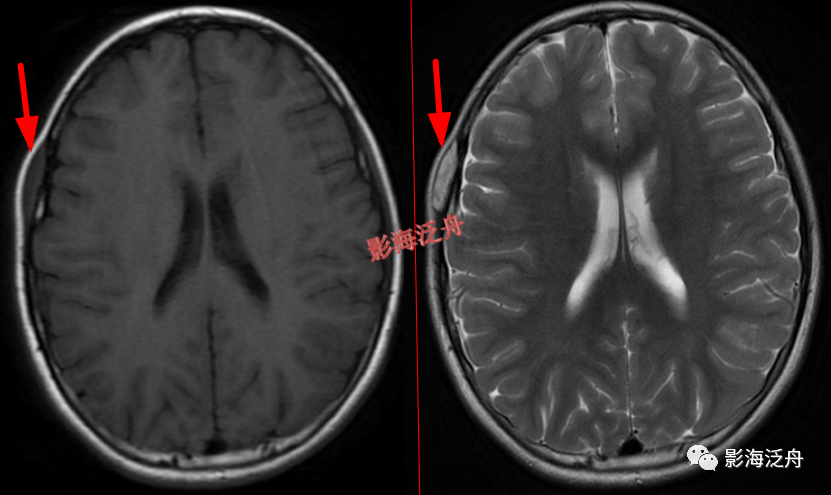

左侧颞部脑膜瘤

,在T1WI、T2WI、Flair、DWI四个序列上都非常接近脑实质的信号。这么小的脑膜瘤在MR平扫上漏诊率极高,避免漏诊的办法就是把颅脑解剖学好,然后看片子的时候把脑沟快速地捋一遍,脑沟发生形态改变的区域重点观察。

右侧侧脑室体部囊性占位(红箭),整体信号与脑脊液一致,病灶边缘部分显示,透明隔稍移位。

灰质移位,患者既往有癫痫

病史。右侧侧脑室前角及左侧侧脑室后角可见异位的灰质结节(红箭),与大脑皮层下的灰质信号一致(绿箭),灰质异位患者多伴有癫痫症状。

透明隔缺如,我自己漏诊过的病例。上面有很多正常的图像可供对比观察。